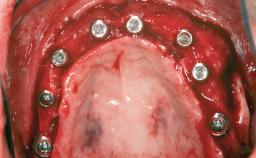

Shell Technique for Horizontal and Vertical Maxillary Bone Augmentation in a Partially Edentulous Patient with Aggressive Periodontal Disease

A 46-year-old woman was referred for treatment whose main complaints were mobility of her fixed partial dentures (right maxilla and left mandible) and periodontal bleeding during function. She also reported having taken systemic antibiotics to treat recurrent swelling in the area of the upper left molars. The patient had not seen a dentist for at least 2 years. She did not smoke and had no history of major systemic disease other than two minor orthopedic procedures some years back. The first-visit examination revealed poor plaque control, tooth mobility, periodontal disease, and a residual dentition widely associated with deep periodontal pockets.

# of Implants 3

Type of Implants One-Piece

Bone Augmentation Horizontal|Staged|Vertical

Augmentation Materials Autogenous chips|Autogenous block(s)|Xenogenous